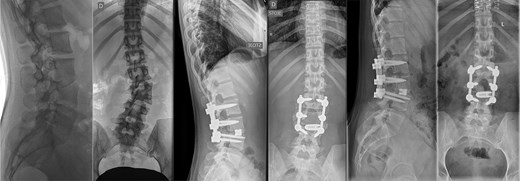

Preoperative CT demonstrating L3 hemivertebra; anteroposterior view (A) on the left side of the image, and lateral view (L) on the right side of the image.

A 43-year-old female with a history of a previous isolated right-sided L3 foraminotomy at an external facility (this intervention temporarily alleviated her leg pain but exacerbated her back pain) was referred to our institution due to chronic back pain, right-sided leg pain without neurological dysfunction, and a forward-leaning posture, which was correctable with verbal cues. The back pain, in the absence of neurological deficits, began 13 years prior, at which time she was diagnosed with adult congenital scoliosis caused by L3 hemivertebrae (Figs 1 and 2). Imaging confirmed a L3 hemivertebra resulting in a 24° Cobb angle of congenital scoliosis (Fig. 1), without associated cord abnormalities on MRI.